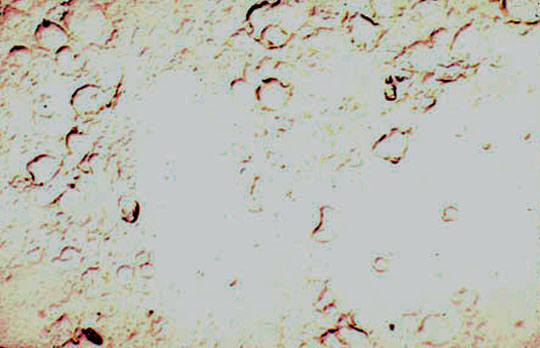

- Blood smear showing polychromasia-a sign of reticulocytosis

Dr Harry Messmore